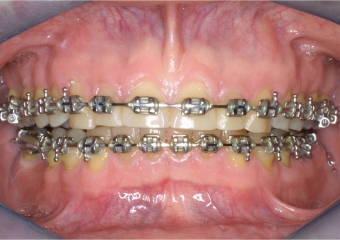

Mordida inicial

Mordida após a remoção do aparelho